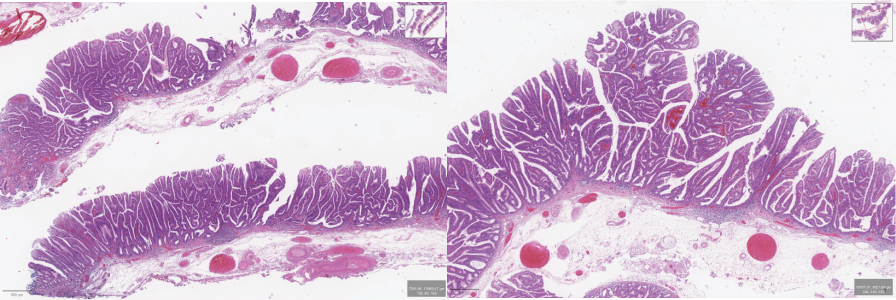

Giải phẫu bệnh

Kết quả mô bệnh học cho thấy tổn thương là u tuyến ống – nhung mao, có loạn sản độ cao. Đặc biệt, diện cắt đáy và diện cắt bên đều âm tính, tức là không còn tế bào u tại bờ phẫu tích. Điều này khẳng định ca ESD đã cắt trọn tổn thương một cách triệt để, không cần phẫu thuật bổ sung. Như vậy, mặc dù bệnh nhân trải qua nhiều biến cố hậu thủ thuật, nhưng về mặt đánh giá thủ thuật, đây là một ca điều trị thành công, loại bỏ hoàn toàn một tổn thương tiền ung thư có nguy cơ tiến triển.